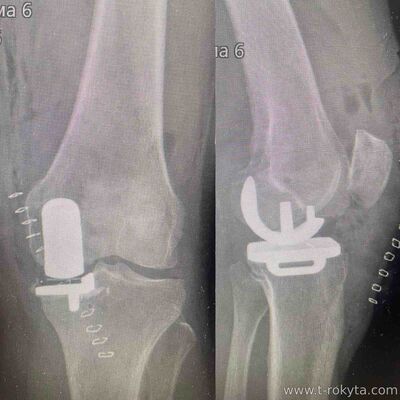

Часткова заміна колінного суглобу або одномищелкове ендопротезування коліна не є частою операцією. Але це операція яка , при правильних показах, дає високі проценти "задоволеності " пацієнтів і це є вищим чим після тотального ендопротезування. Це досить філігранна операція при якій замінюється тільки уражений артрозом хрящ. |

Часткова заміна латеральних відділів колінного суглобу - досить рідка операція. За рік в Україні виконується не більше 5 таких операцій.